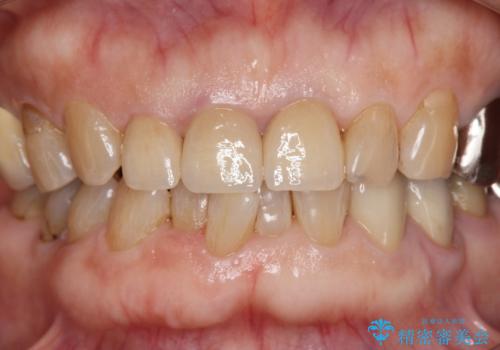

前歯の審美改善

- 70代女性

- 1ヶ月

- 2-5回

- 40万円(仮歯・ファイバーコア・ジルコニアクラウン×3)費用は治療当時の料金となります

セラミック治療は外から見えるのはクラウンの色味・形態、歯肉の状態のみですが、X線撮影において現れるクラウンと歯牙の適合や、ファイバーコアの精度・根管充填の密度に、より長い予後を達成するための要素が含まれると考えます。